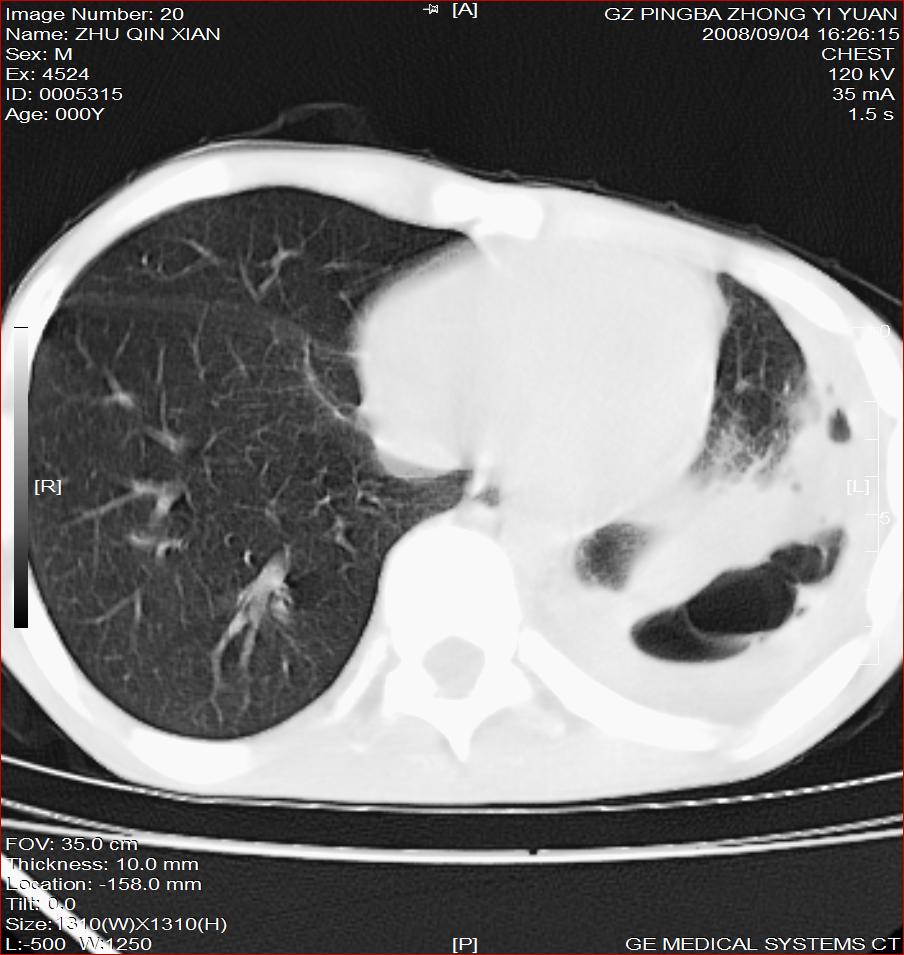

以下是引用随光逐影在2008-9-4 20:05:00的发言:[br]1)考虑两肺结核。2)左侧胸膜炎(胸膜肥厚、粘连,胸腔积液)。3)左侧局限性气胸。

以下是引用子十在2008-9-4 19:34:00的发言:[br]左上肺结核并空洞及双肺播散。节段性肺不张、胸腔积液、胸膜肥厚粘连。[br]